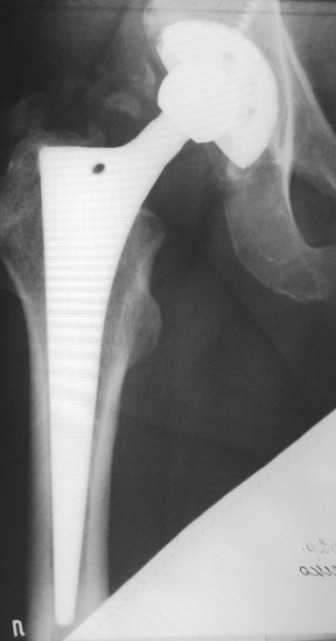

Мне кажется, что это - перипротезный остеолиз, хотя на снимке вокруг ножки явного криминала не видно. С другой стороны, если бы он был виден, то это можно рассматривать как показание к ревизии уже сейчас, а не тогда, когда случится парапротезный перелом. Я бы попробовал миакальцик. Если от него будет снижение болей (а он действует быстро, но только пока вы его даете), то тогда можно планировать более долгосрочную терапию.

Проблема не в протезе, это очень хороший протез Трилоджи-Версис ЕТ и имеются четкие признаки остеоинтеграции. Ищите другие причины болевого синдрома - тенопатия ягодичных м-ц, остеохондроз позвоночника и т.д.